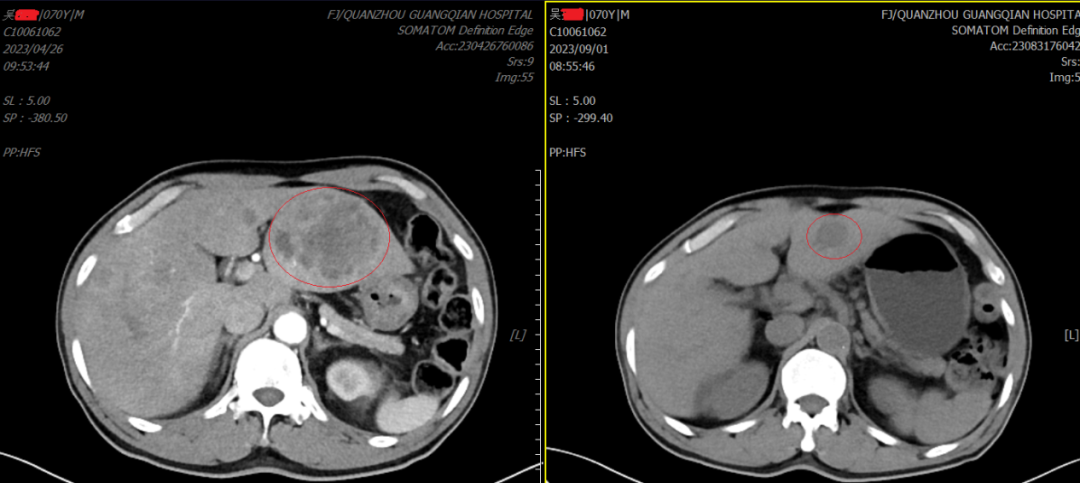

下圖是我院腫瘤放療一區(qū)邱家烷主治醫(yī)師在浙江省腫瘤醫(yī)院花永虹、姜鋒教授指導(dǎo)下完成的對蔡阿伯軟腭癌,誘導(dǎo)化療+免疫治療的治療效果圖,目前正在行同步放化療……